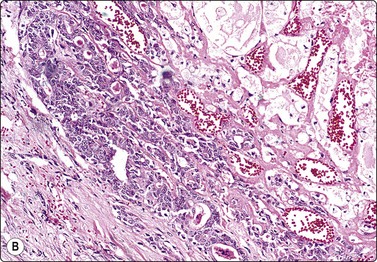

image image

Fig. 7.3 Non-neoplastic glandular breast tissue and low-grade duct carcinoma

High-power view, air-dried smears; (A) Non-neoplastic glandular breast tissue; (B) Low-grade duct carcinoma. Note single bipolar nuclei in A, and absence of bipolar nuclei, relatively mild nuclear atypia and some loss of cohesion of malignant cells in B (MGG, HP).